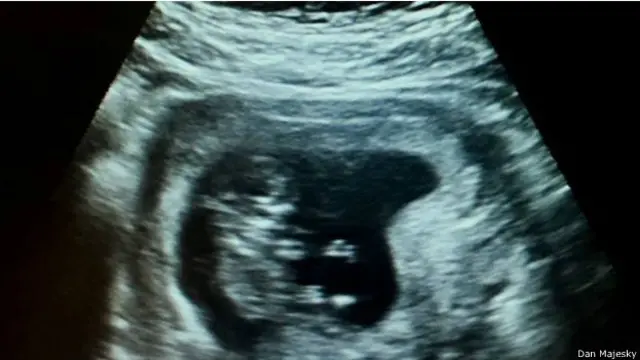

Sebagai bagian dari tulisan di Facebook, pasangan itu menyertakan hasil USG bayi mereka yang berusia 15 minggu di kandungan dan dijadwalkan lahir pada November mendatang.